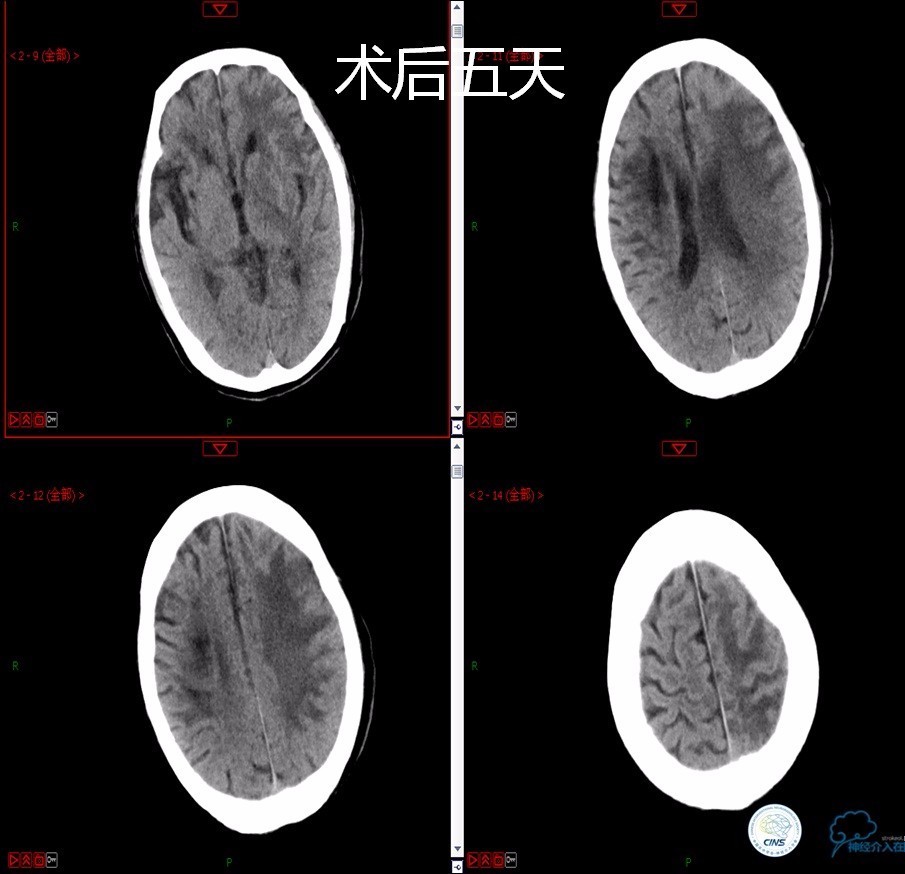

》男,79岁。

》主诉:阵发性头晕伴双下肢无力一年余。

》查体:左侧上肢肌力Ⅱ级, 双侧下肢肌力Ⅲ级。

》既往史:高血压、糖尿病史。

》术后严密控制血压,未出现明显血压波动。

》术后三小时,患者出现恶心呕吐,伴有意识丧失。

》出血原因?侧支代偿不佳!